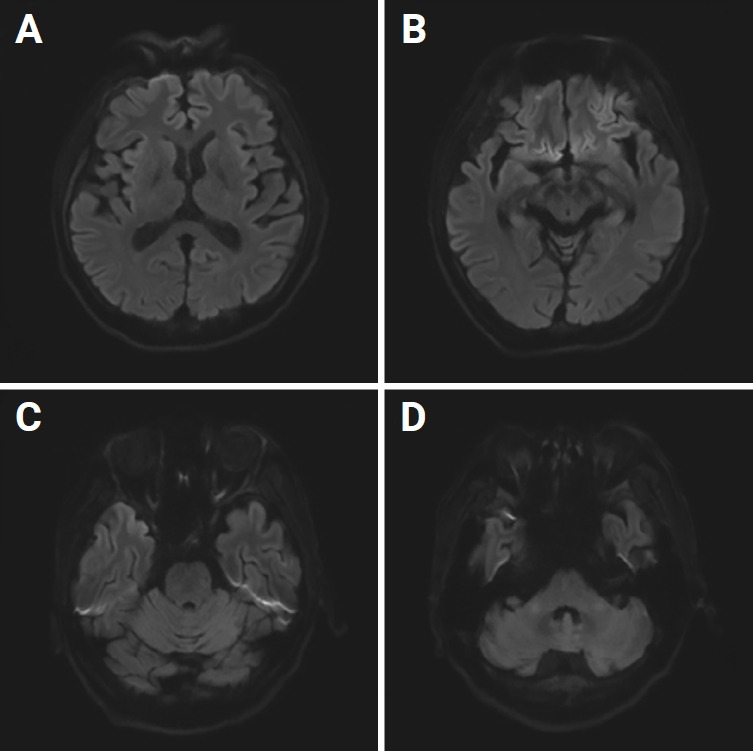

Osmotic demyelination syndrome (ODS) is an acute demyelinating disorder characterized by the loss of myelin in the center of the basis pons, defined as central pontine myelinolysis (CPM), and demyelination in locations outside the pons, defined as extrapontine myelinolysis (EPM). ODS including CPM and EPM is mainly caused by rapid correction of hyponatremia. However, there are several reports of ODS in medical conditions such as malnutrition; alcoholism; liver transplantation; malignancy; sepsis; and electrolyte imbalance including hypernatremia, hypokalemia, hypophosphatemia, and chronic illness. ODS caused by rapid correction of hyperammonemia or continuous hyperbilirubinemia without sodium fluctuations has rarely been reported. Because ODS may be irreversible, prevention is crucial. Herein, we report a case of ODS secondary to rapid correction of hyperammonemia and continuous hyperbilirubinemia.

Abstract Image